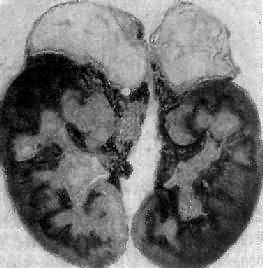

引起本病的病因主要有双侧肾上腺结核(图15-15)和特发性肾上腺萎缩,偶尔也可因转移引起。特发性肾上腺萎缩(idiopathic adrenal atrophy)是自家免疫性炎症,故又称自家免疫性肾上腺炎(autoimmue adrenalitis),多见于青年,女性显著多于男性。病人血中常有抗肾上腺皮质细胞线粒体或微粒体抗体,常与其他自家免疫性疾病合并。双侧肾上腺高度萎缩,共重2.5g以下;皮质菲薄,镜下除皮质萎缩外,有大量淋巴细胞和浆细胞浸润。

双侧肾上腺结核

图15-15 双侧肾上腺结核